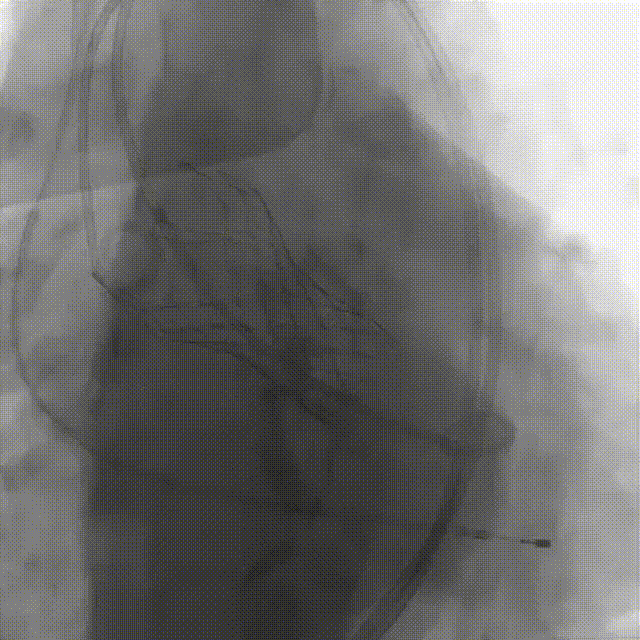

刘煜昊教授 阜外华中心血管病医院(点击查看专家详细简历) 首瓣选耐久,干瓣护航全生命周期管理 2025年ESC专家共识里指出:“推荐第一个瓣膜要选经证实具有长期耐用性的外科瓣膜与经导管瓣膜,以降低再次介入治疗的可能性 ,对于瓣环较小、根据预测有效瓣口面积(EOA)评估存在严重 PPM 风险的患者,可采用主动脉根部扩大术联合 SAVR,或植入环上瓣,对于小瓣环患者自展瓣拥有比较好的血流动力学优势”。 每一次术前评估,都是我们与患者携手面对未知的起点。我们始终以患者全生命周期获益为核心,在瓣膜选择与术式规划中,不只着眼于当下解剖适配,综合评估解剖条件、预期寿命与生活质量。从年轻患者到高龄人群,瓣膜耐久性与血流动力学稳定性始终是决策核心! 陈同峰教授 阜外华中心血管病医院(点击查看专家详细简历) 医学的进步正不断拓宽生命的边界,每一次术前评估都是对生命尊严的深度凝视,技术与人文的交融,让风险不再仅是数字的堆叠,而是成为医者与患者共同面对未知的勇气见证。术中瓣膜释放结束,到了导管测压的时候,我惊喜:瓣膜不错啊,压差为0,这不仅仅得益于瓣膜形态的设计,更是环上瓣及瓣叶材质优质的体现,感受到了 Prostyle A瓣膜在血流动力学上的卓越表现,其采用的抗钙化处理技术有效延长了瓣膜的耐久性,为患者长期生存提供了更可靠的保障。 患者病史 主诉:心慌半月; 门急诊诊断:心悸,冠状动脉粥样硬化性心脏病,心脏瓣膜病,主动脉瓣狭窄,高血压,甲状腺术后; 现病史:半月前无明显诱因出现心慌,呈间断性,伴心悸、出汗,伴头晕,无咳嗽、咳痰,无恶心、呕吐,无双下肢水肿,无放射痛及意识障碍,休息约几分钟后可自行缓解,症状反复发作,遂来我院就诊。 术前超声提示:室间隔增厚;主动脉瓣退行性变并重度狭窄;升主动脉明显增宽;室间隔增厚。 术前CT 三叶瓣,轻度钙化集中在无窦和左窦瓣叶边缘,主动脉根部直径19.3mm,LVOT直径17.7mm,LVOT向下收窄; 窦部正常,VTC空间足够,冠脉风险低; 左室腔小,收缩末径20-25mm,“自杀左室”,循环崩溃风险高;主动脉瓣环水平夹角71.1°,横位心,过弓和跨瓣存在一定困难,备snare。 外周双侧入路内径可,双侧入路能够支持20F大鞘通过,右股低分叉。 手术策略 推荐右侧股动脉为主入路,左侧为辅助入路,右股分叉上方1cm穿刺;推荐选择AV23瓣膜,18mm球囊预扩,左右重叠位:LAO 7° CAU 35°;左冠切线位:LAO 27° CRA 16°;右窦居中位:LAO 18° CAU 9°;备Snare,建议ECMO/CPB湿备,术前术中积极补液,警惕循环崩溃风险。 手术过程 在右股动脉穿刺建立通路后,顺利送入大鞘,经食道超声及血管造影确认路径稳定。18mm球囊预扩过程中,患者血压一度下降,迅速完成扩张并立即植入AV23 ProStyle A®瓣膜。瓣膜精准释放于目标位置,超声显示无明显反流及瓣周漏,血流动力学即刻改善。 主动脉根部造影 18mm球囊预扩少量反流 输送系统柔顺跨瓣 精准定位 平稳释放 80%工作位观索位置合适 释放后导管测压,压差由术前53mmHg降为0mmHg 最终造影瓣膜位置形态良好,冠脉灌注良好,无明显瓣周漏 ProStyle A®预装干瓣——助力临床最优化解决方案: 轻松过弓,精准可控:该病例为横位心,在未使用snare的情况下,过弓和跨瓣柔顺,较细的尺寸+柔顺的输送系统通过性能得到了很好的验证; 平衡的收腰设计:该病例瓣环较小且左室腔小,AV23瓣膜的平衡收腰设计既确保了锚定安全性,又保证了EOA,有效降低了循环崩溃风险,而术后0mmHg的压差的表现更加证明了优秀的血流动力学,提高了瓣膜的耐久性; 预装干瓣 便捷顺安:金仕生物专利抗钙化技术运用纳米技术去除组织内的细胞碎片和磷脂,封闭游离醛基,从根本上阻断了瓣膜钙化的多项因素,显著提升了瓣膜的耐久性;同时,相比较传统戊二醛保存方式,干式存储最大限度的保留心包的亲水亲油平衡,还原组织天然曲柔性,进一步保障了瓣叶开合,保证长期耐久性。 专家简介 王小虎 阜外华中心血管病医院(点击查看专家详细简历) 陈冲 阜外华中心血管病医院(点击查看专家详细简历) 赵一品 阜外华中心血管病医院(点击查看专家详细简历)